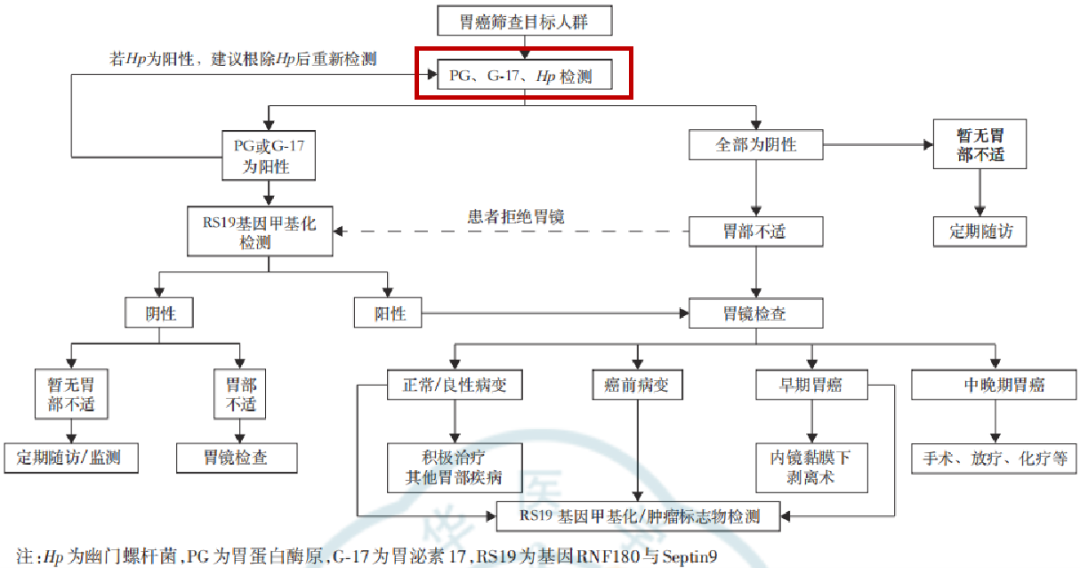

ж–°е…ұиҜҶгҖҠдёӯеӣҪж—©жңҹиғғзҷҢзӯӣжҹҘзЈЁз»ғжүӢиүә专家е…ұиҜҶгҖӢжҺўи®ЁдәҶеӨҡз§Қеёёи§Ғзҡ„ж—©жңҹиғғзҷҢзЈЁз»ғжүӢиүә�гҖӮ�гҖӮжң¬зҜҮж–Үз« еёҰдҪ дёҖиө·и§ЈиҜ»ж–°е…ұиҜҶ�пјҢ�пјҢ�пјҢпјҢзӣёиҜҶж–°е…ұиҜҶзҡ„дёүеӨ§йҮҚзӮ№йғЁеҲҶпјҡж—©жңҹиғғзҷҢзҡ„зЈЁз»ғжүӢиүәгҖҒж—©жңҹиғғзҷҢзҡ„жЈҖжҹҘж Үи®°зү©гҖҒж—©жңҹиғғзҷҢзҡ„зӯӣжҹҘжҺЁиҚҗжөҒзЁӢ�гҖӮ�гҖӮ